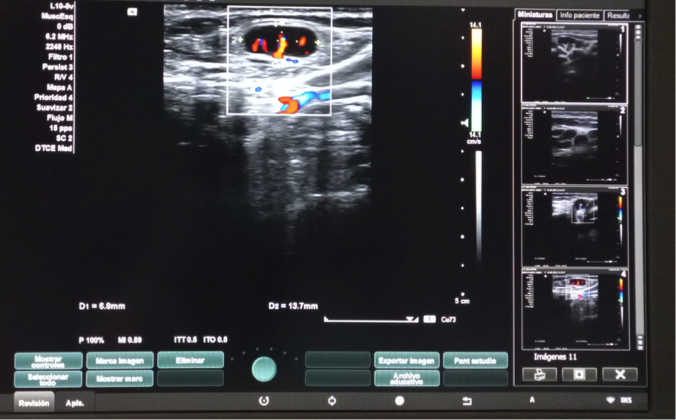

Hallazgos ecográficos

Dos adenopatías en territorio laterocervical derecho, con hilio central y doppler positivo, alguna con diámetro transversal superior al longitudinal, de probable origen reactivo y una adenopatía supraclavicular sin hilio central y con vascularización generalizada.

A las dos semanas de iniciar el tratamiento con ibuprofeno, se realiza el control ecográfico que evidencia ganglios cervicales bilaterales, inespecíficos de probable carácter reactivo y menores de 10 mm en el eje corto, por lo que finalmente se decide no exéresis de adenopatía.